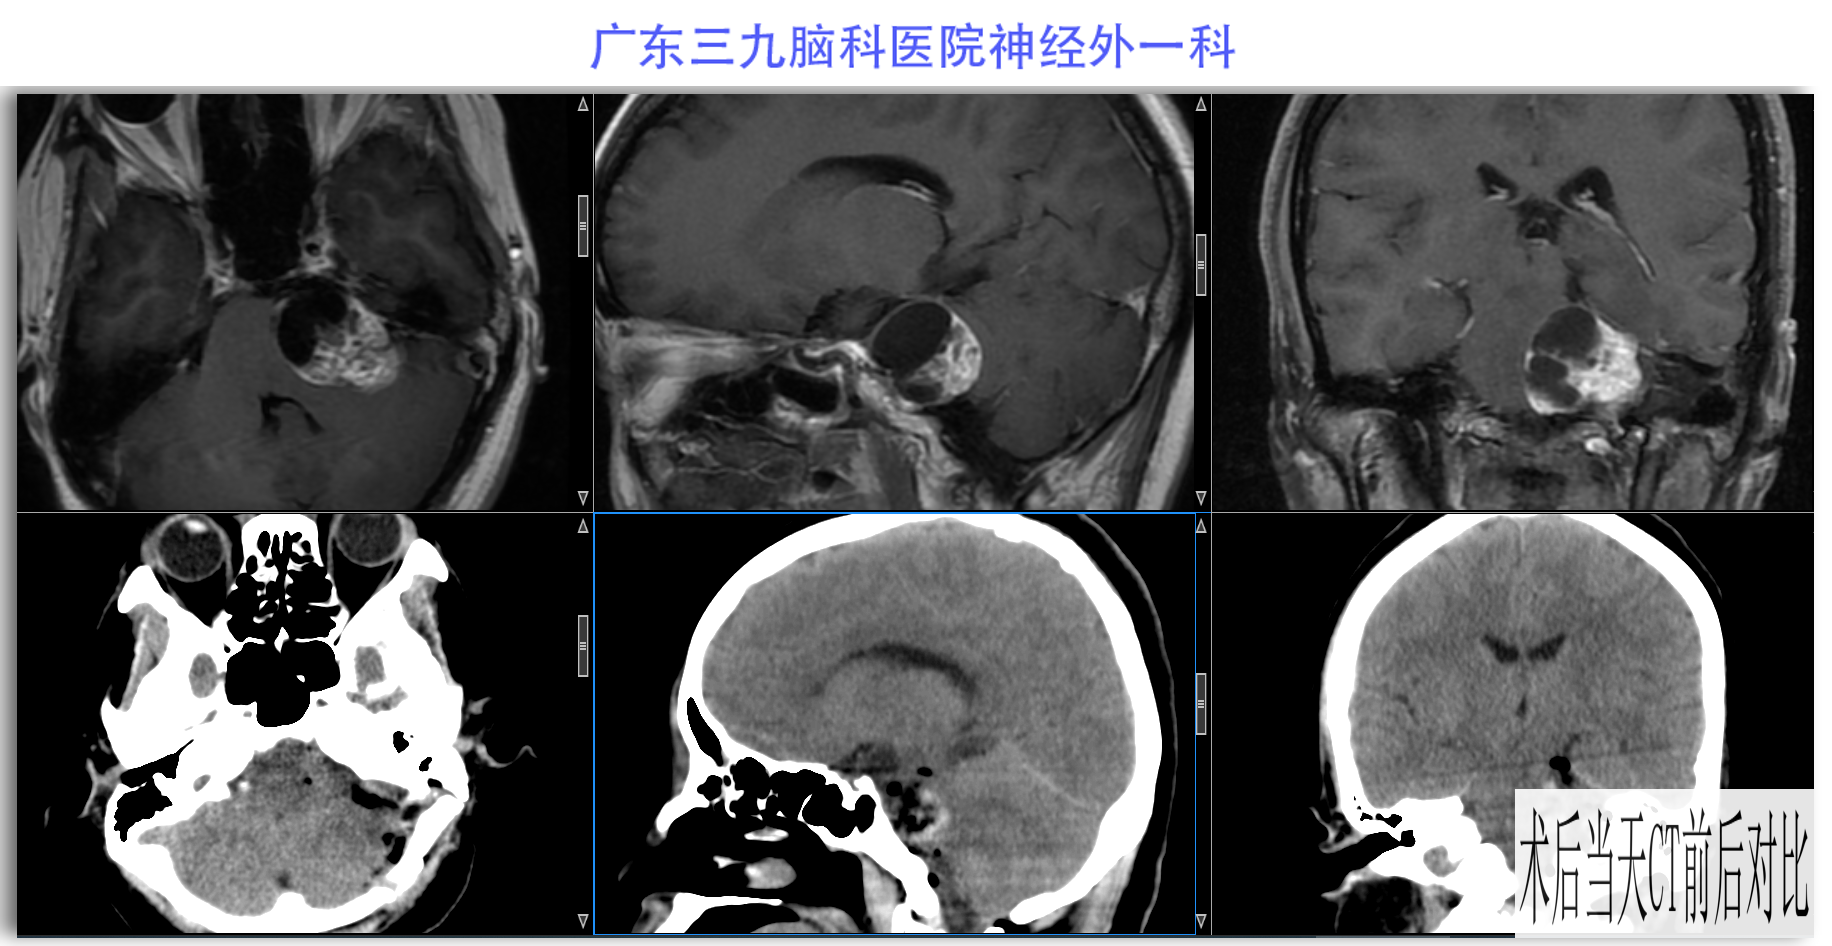

陈某某,女,41岁,因“左侧面部麻木3月余,吞咽困难半月余”于2024-02-17入院。患者3个月前出现左侧面部麻木,偶尔伴有头晕和左侧流泪,但没有听力下降或耳鸣。同时,患者也出现肢体乏力和行走不稳,但未接受任何治疗。半个月前,患者发现吞咽硬质食物稍有困难,同时左侧面部麻木加重。因此,前往当地医院就诊,并进行头颅MR检查,结果显示左侧CPA区存在占位性病变。为了进一步治疗,患者转诊至我院就医。术前检查显示:左侧角膜反射减弱,左侧鼻唇沟略微变浅,伸舌稍微右偏,咽反射迟钝。门诊诊断为“左侧巨大听神经瘤”,收治至我科进行住院治疗。手术过程顺利,术后患者恢复良好,面部轻度瘫痪与术前相同。术后病理检查结果确认为听神经瘤。